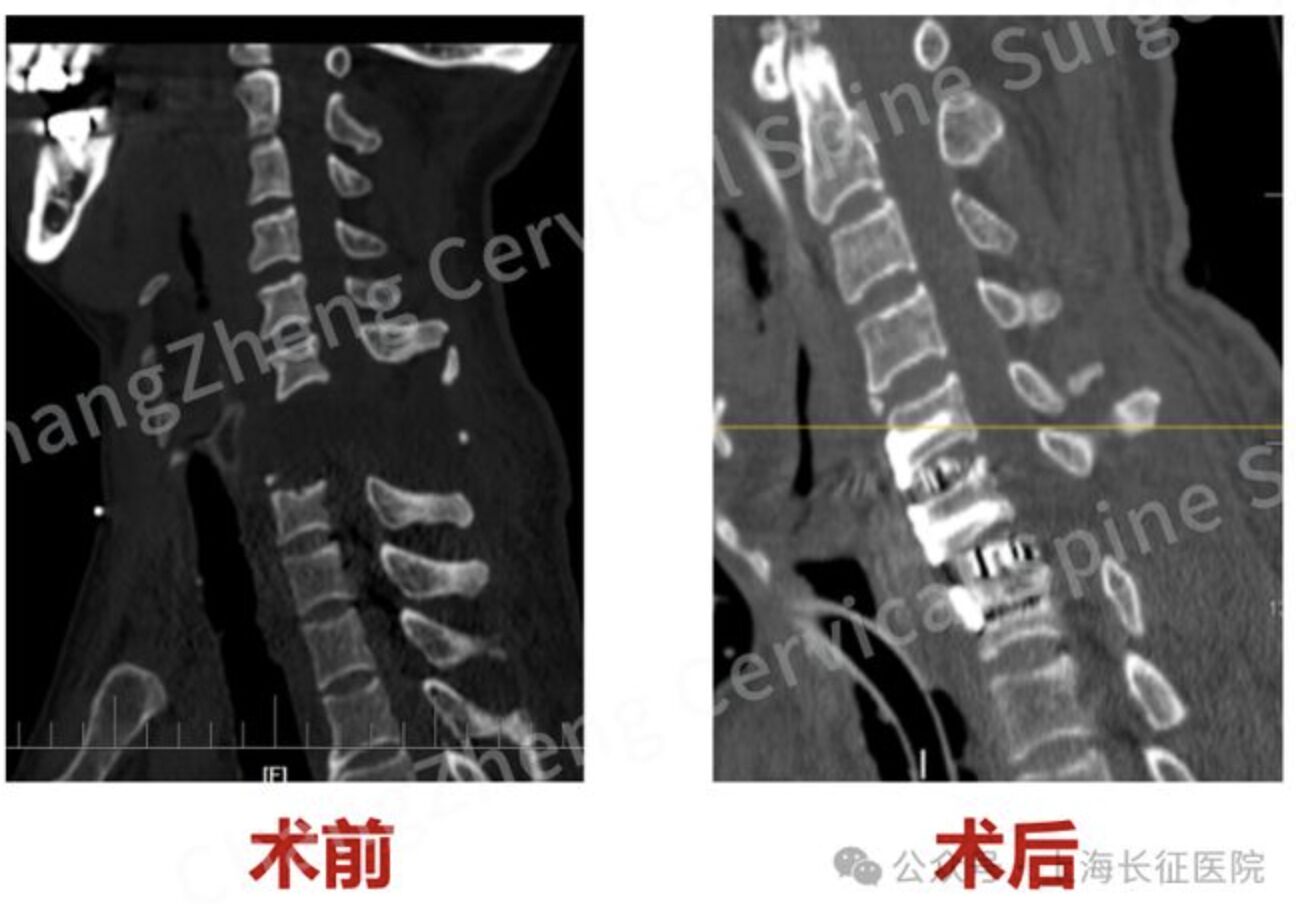

由於患者頸椎前後骨與軟組織「全斷」,且頸後皮膚大面積破損、腦脊液大量外漏,後路或前後聯合路徑感染風險極高;在無法完成更進一步影像檢查的情況下,手術必須「邊開邊判讀」。團隊以顯微操作清除血腫與嚴重沾黏,採前路復位+創新「衛星鋼板」輔助固定,在常規鋼板之外加設輔助固定點,提升整體穩定度,最終於約3小時內完成復位重建並控制出血風險。

術後患者進入重症監護,醫療團隊持續進行器官功能維護,隨後50餘天內又完成十多次骨修復、清創等手術。7月31日,患者已脫離呼吸器並轉入燒傷整形科治療,主要臟器功能恢復、四肢可活動且可書寫溝通。醫師提醒,此類高處鈍擊或高能量損傷,死亡與重殘風險極高,現場處置宜立即撥打急救、避免搬動,以免二次損傷。